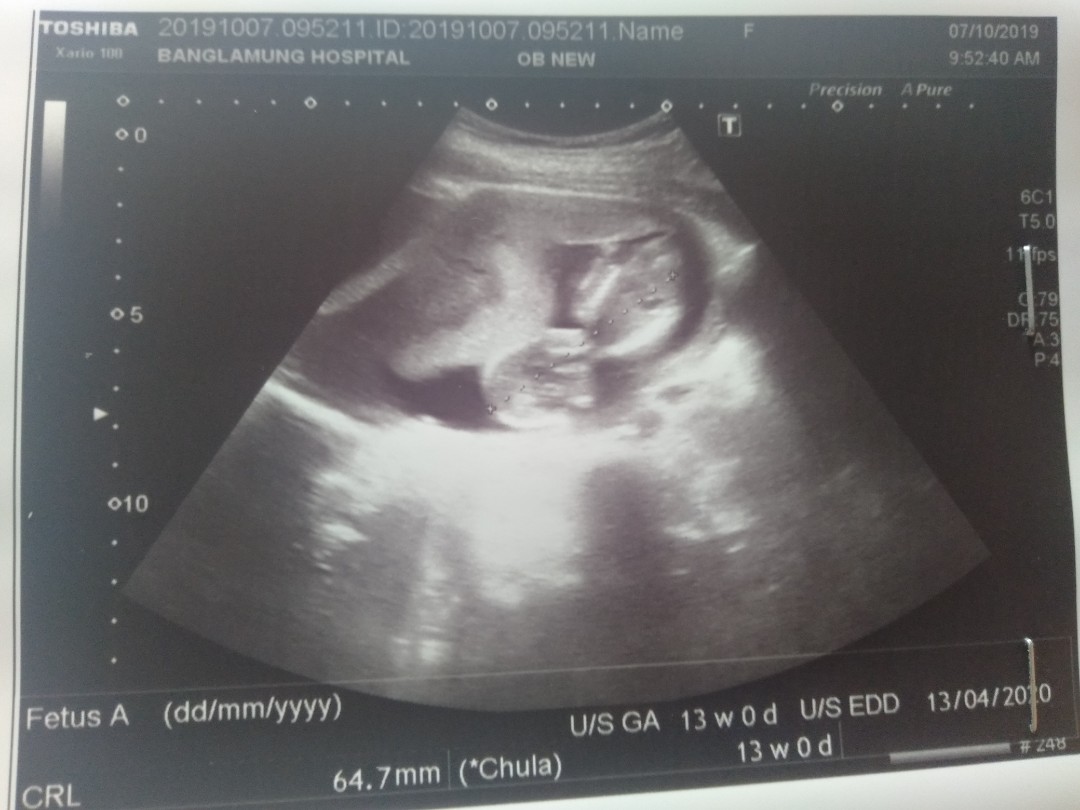

13 วีคจ้า

13วีคค่ะ